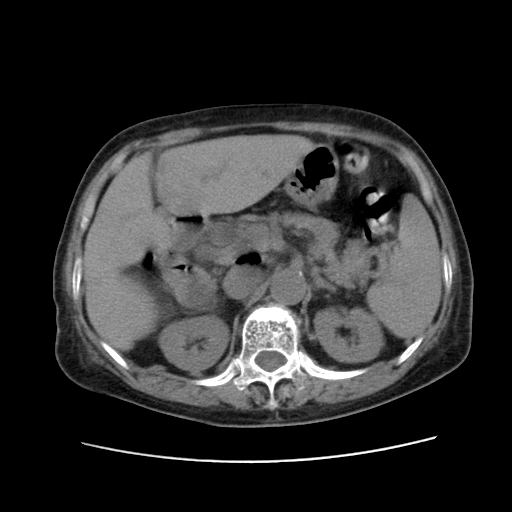

标题: CT25203:上腹部增强,看看

女,77.无不适

胆总管扩张

肝旁多发胆囊状液体影考虑肠腔积液基中部分囊状景不多外胆囊

肝右叶肝内胆管结石并肝内胆管扩张。胆总管下段梗阻,考虑壶腹部占位。

肝右叶肝内胆管结石并肝内胆管扩张。胆总管下段梗阻,考虑壶腹部占位。支持